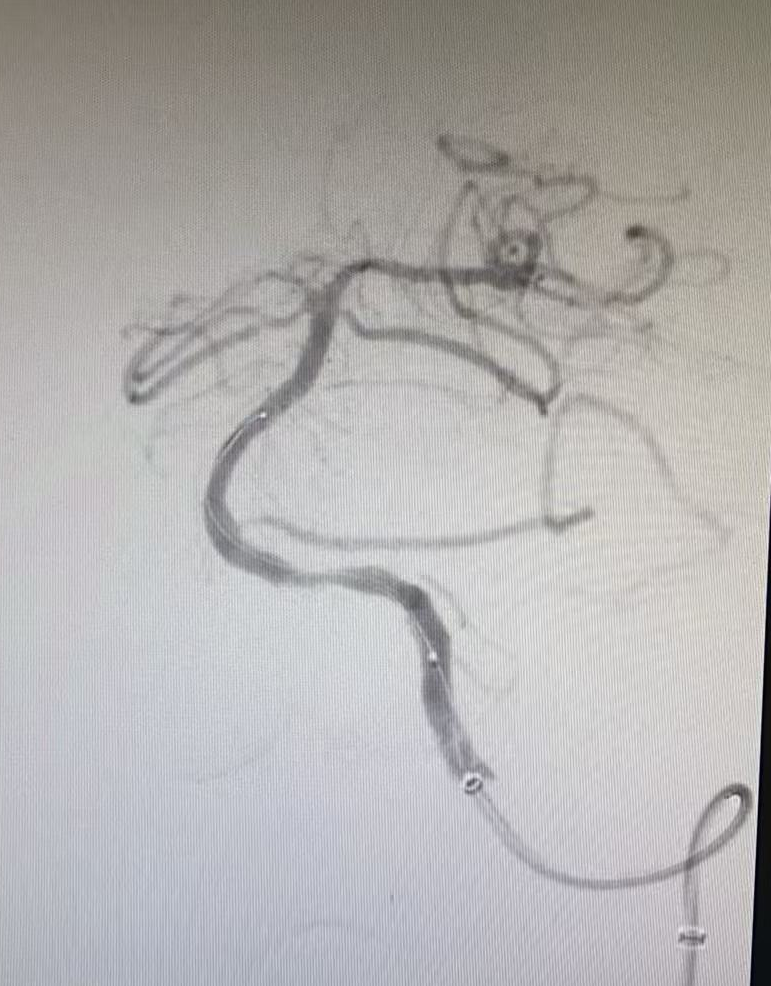

但挑戰(zhàn)還在繼續(xù),血管開通后發(fā)現(xiàn)內(nèi)部存在嚴(yán)重狹窄,遠(yuǎn)端血流灌注不足,團(tuán)隊隨即進(jìn)行球囊擴(kuò)張改善血流,但血管回縮明顯。為確保持久通暢,團(tuán)隊果斷植入一枚支架。最終,血管形態(tài)恢復(fù)良好,血流達(dá)到最佳標(biāo)準(zhǔn),缺血的大腦獲得了充足的血液供應(yīng)。

球囊擴(kuò)張術(shù)后